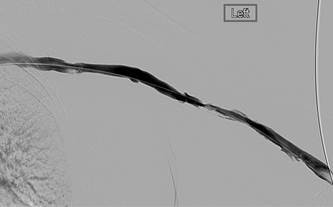

Thrombectomy of left brachiocephalic AV fistula

Initial central venogram confirming patency of central veins.

Underlying stenosis in cephalic arch responsible for thrombosis.

Fistulogram following 1st pass with an AngioJet DVX catheter (NB: no thrombolytics used).

Fistulogram post 2nd pass with DVX catheter. A further mid-AVF stenosis has been identified.